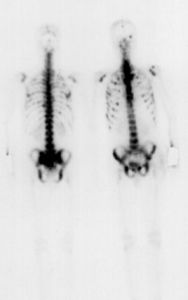

肺癌骨轉移早期一般無任何症狀,骨同位素掃描ECT可早期發現有病變的骨骼。

肺癌骨轉移症狀:骨轉移早期一般無任何症狀,骨同位素掃描可發現有病變的骨骼。骨轉移症狀與腫瘤轉移的部位、數量有關,如肺癌肋骨轉移引起的胸痛,多表現為胸壁部位局限的、有明確壓痛點的疼痛。脊髓轉移引起後背部正中或病變部位疼痛,而四肢或軀幹的骨轉移引起該部位的局限性疼痛。骨轉移並非威脅肺癌病員生命的直接原因,但如腫瘤轉移到機體承重骨如頸椎、胸椎、腰椎等部位則可造成癱瘓的嚴重後果。因此對肺癌出現骨轉移患者應及時治療。治療